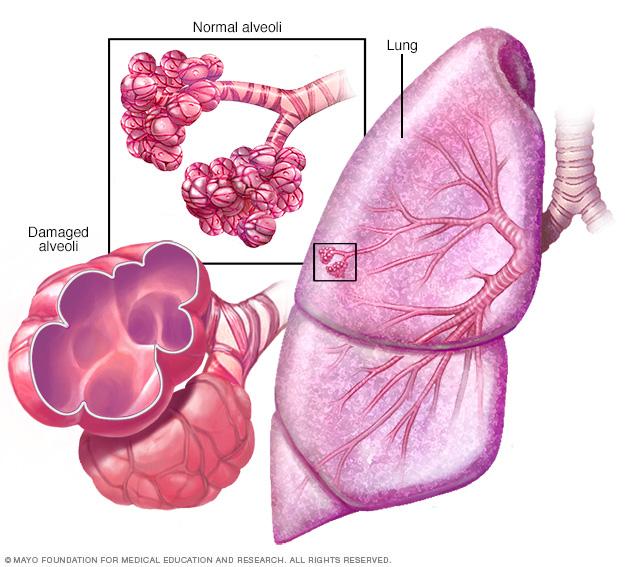

Emphysema

In emphysema, the inner walls of the lungs' air sacs called alveoli are damaged, causing them to eventually rupture. This creates one larger air space instead of many small ones and reduces the surface area available for gas exchange.

- Emphysema. This lung condition causes destruction of the fragile walls and elastic fibers of the alveoli. The damaged inner walls of the alveoli may be destroyed, creating one large air space that is hard to empty compared with the many healthy small ones. The alveoli now have less surface area that can be used to exchange oxygen and carbon dioxide. Also, old air gets trapped in the large alveoli so there isn't room for enough new air to get in.